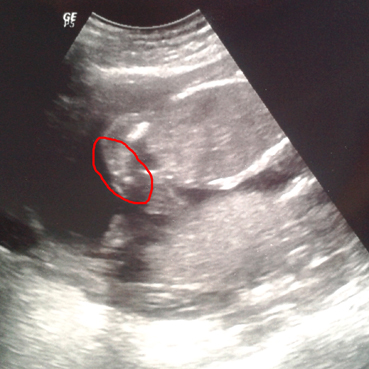

I had an ultrasound today and the doctor told me that my baby could be a girl, because she couldnīt see a penis. And then she saw 3 white dots...Everything is still very little and unsharp so she didntīt want to say "100%"

So do you girls moms think itīs a girl? Did it look like that with your girls?